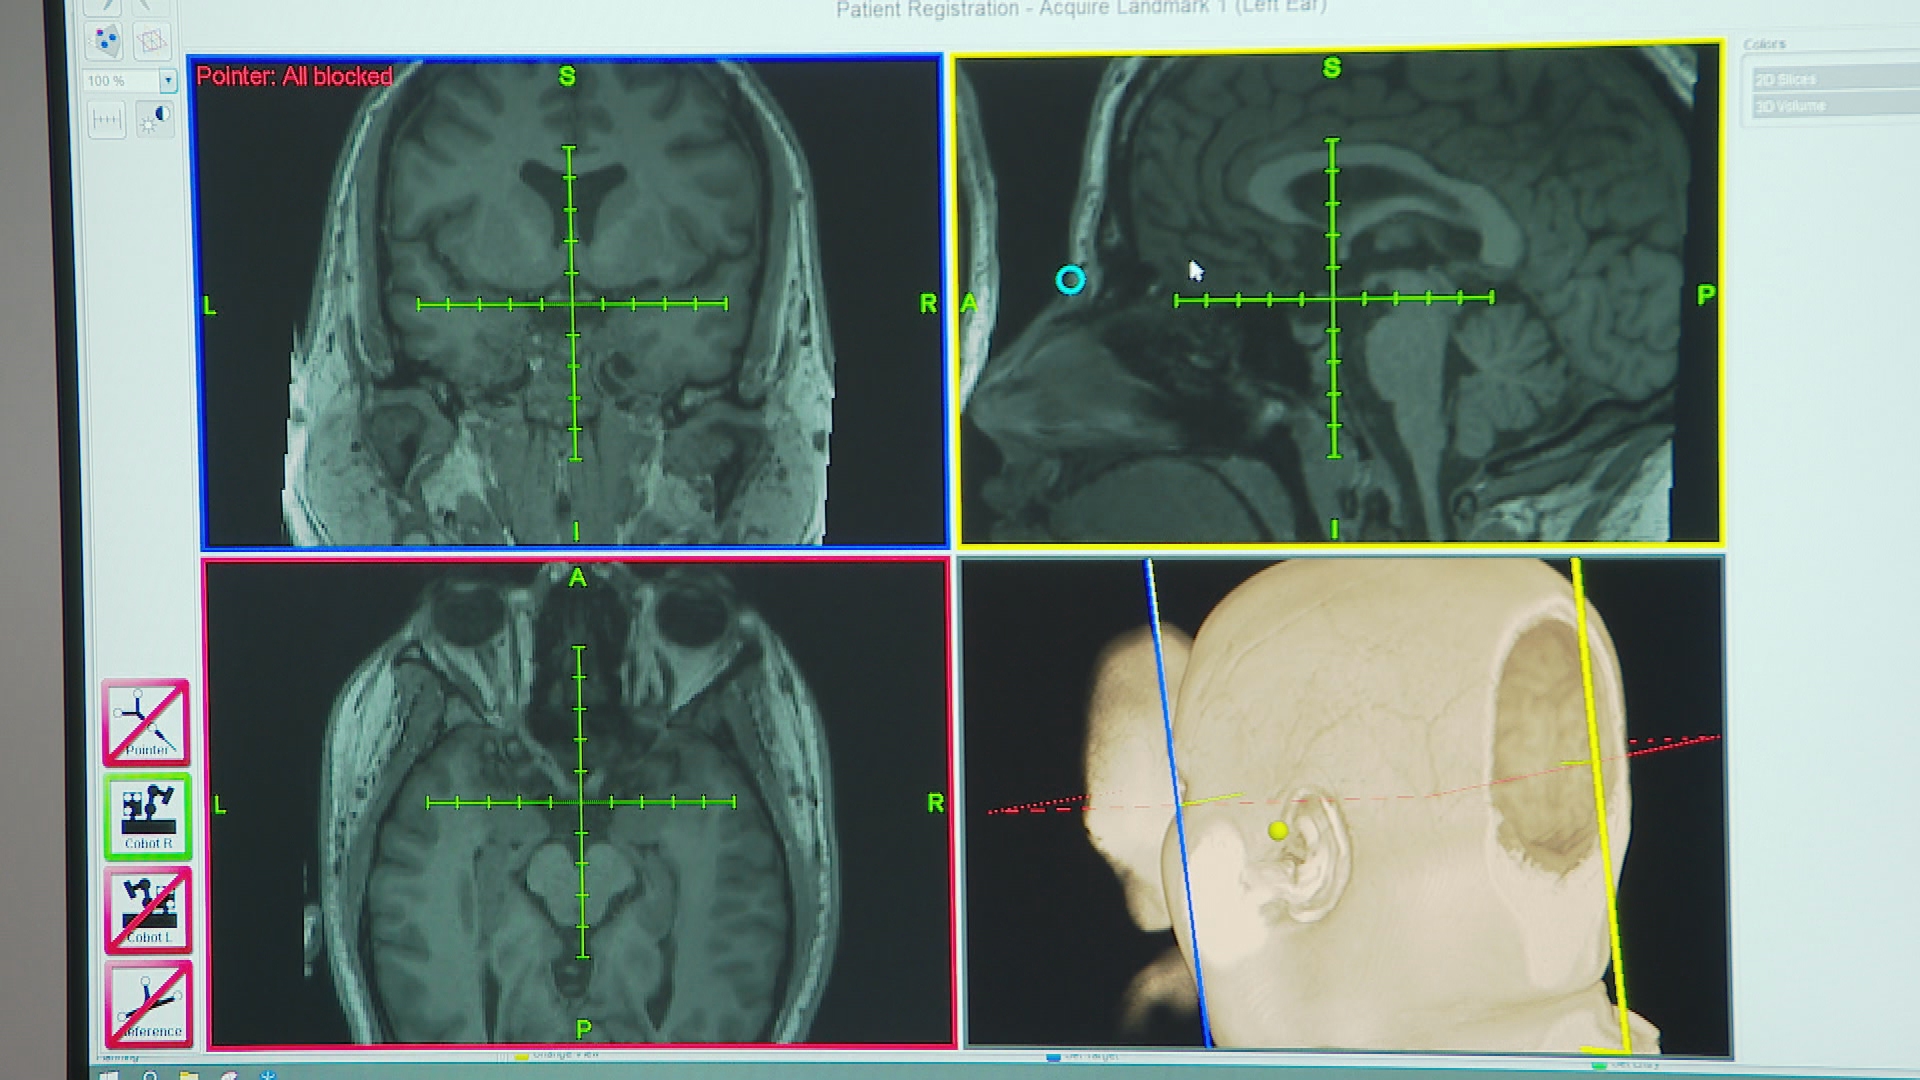

Researchers like Dr Robin Cash from the University of Melbourne use an MRI scan to map specific areas in each patient's brain that are triggering the depression.

The TMS is then sent to that spot with a millimetre of allowance.

"What we're doing is a precise targeted approach that's based on a brain scan," Cash said.